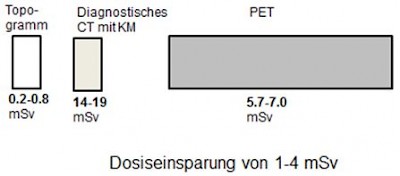

Überlegungen zur Reduzierung der Strahlenexposition:

Falls im Vorfeld der PET-CT Untersuchung eine CT-Schnittbilddiagnostik gelaufen ist, kann man auf das diagnostische CT bei der PET-Untersuchung verzichten. Die Low-Dose CT reicht völlig aus, um die PET-Bilder zu anatomischen Strukturen zuzuordnen.

Falls ein diagnostisches CT bei der PET-Untersuchung notwendig ist, kann man auf das Low-Dose CT verzichten, und das diagnostische CT zur Schwächungskorrektur heranziehen.